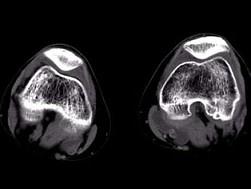

问题 男,48岁,左大腿上段后部轻度胀痛,轻压痛,无明确外伤史,请结合所提供的图像,选择最佳选项 ( )

选项 A、腱鞘囊肿 B、腱鞘脓肿 C、皮脂腺瘤 D、脂肪瘤 E、表皮样囊肿

答案 A